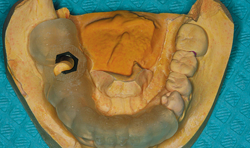

Fig. 1 An intraoral photo shows a patient missing a lower-right first molar

During my initial appointment with a patient, I will capture an image with an intraoral camera (Fig. 1).